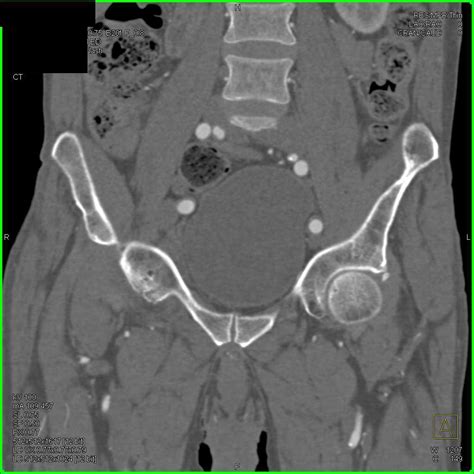

Diagnosing hip joint effusion typically involves a combination of physical examination, medical history, and diagnostic tests. The diagnostic process may include:

• Imaging Tests: X-rays, MRI, or ultrasound to visualize the hip joint and detect fluid accumulation.